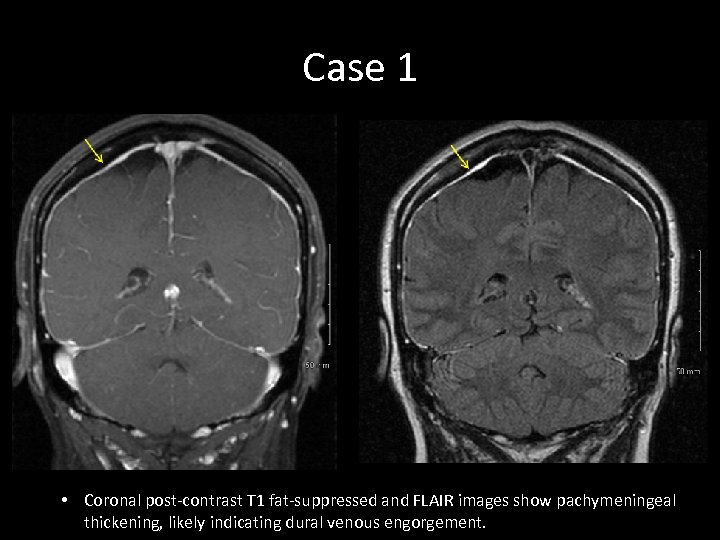

Case 1 • Coronal post-contrast T 1 fat-suppressed and FLAIR images show pachymeningeal thickening, likely indicating dural venous engorgement.

Case 1 • Coronal post-contrast T 1 fat-suppressed and FLAIR images show pachymeningeal thickening, likely indicating dural venous engorgement.